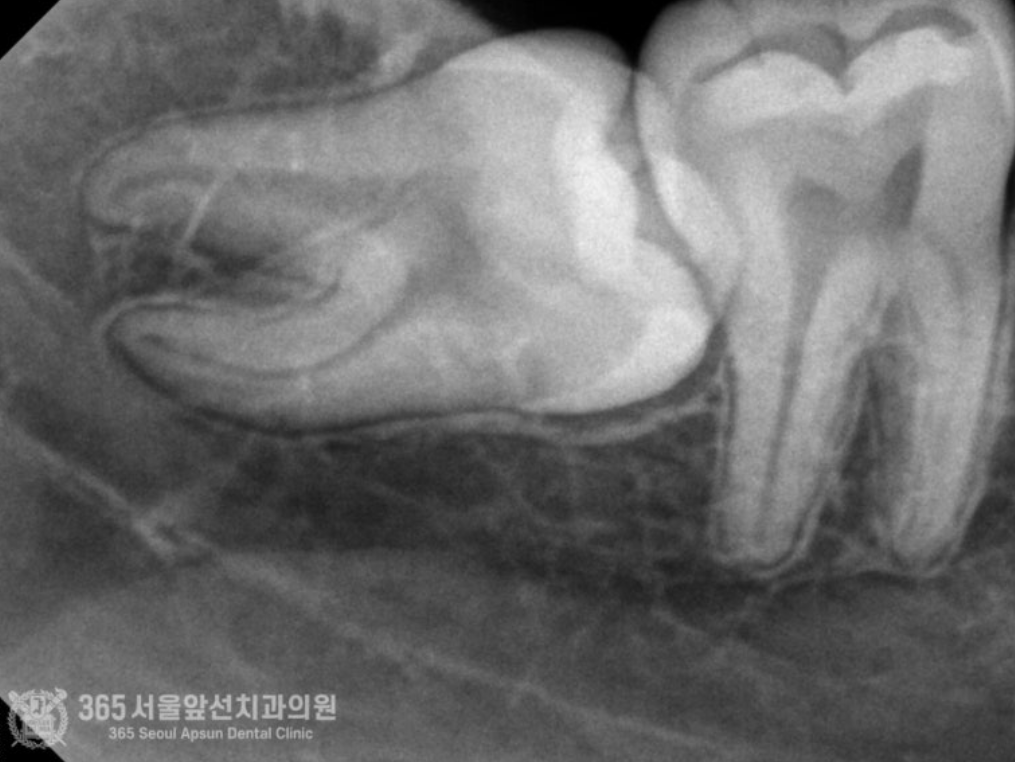

치아교정 전에 양쪽 매복사랑니 발치하고 싶어요. 안녕하세요. 간석동치과 365서울앞선치과의원입니다. 오늘 소개해드릴 치료 증례는 아래턱 수평 매복 사랑니 발치 증례입니다. 상기 환자분께서도 그러한 이유에서 사랑니 발치를 원하셔서 진행하기로 했습니다 ㅎㅎ 촬영일시 : 2024.08.13. 처음 내원 당시 엑스레이 사진입니다. 입안에서 오른쪽 아래턱(사진상 왼쪽 아래 빨간원)에 수평으로 매복된 사랑니가 관찰됩니다. 촬영일시 : 2024.08.13. 정밀한 작은 엑스레이를 촬영했습니다. 사진 상에서 아래쪽에 신경관이 지나가는게 관찰됩니다. 주의해서 발치해야겠습니다. 촬영일시 : 2024.08.13. 발치를 시작한지 6분만에 발치를 완료했습니다. 빠르고 정확한 발치를 통해 환자분의 고통을 줄여드릴 수 있었습니다 ㅎㅎ 촬영일시 : 2024.08.13. 매복사랑니를 세 조각으로 잘라서 발치를 진행해드렸고, 깔끔하게 절단된 사랑니 조각들이 보입니다. 빠르고 정확한 발치에 환자분께서도 만족하셨습니다. 오늘은 6분만에 아래턱 매복 사랑니 발치를 완료한 치료 증례를 소개해드렸습니다. 앞으로도 더 좋은 치료 증례로 찾아뵙겠습니다. 간석동치과 365서울앞선치과의원이었습니다. 감사합니다! [ 치료기간: 2024년 8월13일 ] ※ 365서울앞선치과의원의 모든 포스팅은 각 진료과 의료진이 직접 작성합니다. 365서울앞선치과의원 블로그의 임상 케이스 게시물은 환자분께 의학적으로 정확하고 상세한 정보를 드리기 위해 각 진료과 의료진이 직접 작성하며, 모든 증례 사진은 본원 의료진이 직접 시술한 증례를 촬영한 것으로, 의료법 제23조, 제56조에 의거하며 환자분의 동의를 얻어 포스팅에 사용하였습니다. 또한 해당 케이스는 본 환자분의 치료 결과이며, 환자 상태에 따라 치료의 결과는 달라질 수 있습니다. |